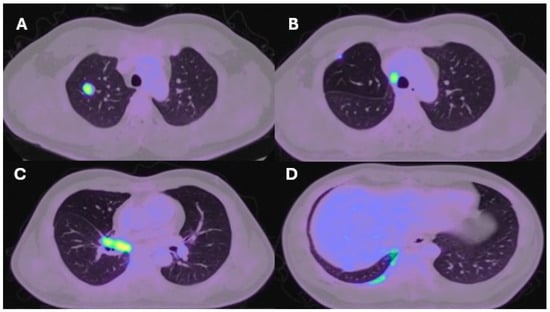

| Lung resection November 2022—Left lower lobectomy + lymph node dissection: pT3pN0 R0 resection. SMARCB1-deficient, PDL1-negative, TTF-1 negative, CD56-positive, cytokeratin positive. Pre-operative CT axial and coronal slices are shown in Figure 2A and Figure 2B, respectively. | Lung resection January 2022—right upper lobectomy + lymph node dissection: pT1cpN0 R0 resection. SMARCB1-deficient, PDL1 negative, TTF-1 negative, CD56-positive, cytokeratin-positive. Pre-operative axial PET slice shown in Figure 3A. |

| Recurrence December 2022—started 4 cycles of Gemcitabine/Cisplatin. Post-operative recurrence demonstrated in PET slices (Figure 2C,D) | Recurrence June 2022—progressive disease noted on CTPA (performed for SOB, pyrexia) at the right hilum, with soft tissue thickening at resection margins. Commenced on Pembrolizumab/Paclitaxel/Cisplatin with systemic intent. Recurrence shown in station 4R (Figure 3B), at the right hilum (Figure 3C) and in the right posterior bony skeleton in ribs 6–9 (Figure 3D). |